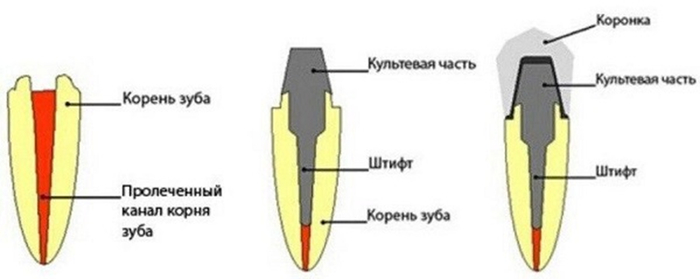

Изготавливают прямо во рту у пациента. Являются, пломбой на штифте, и называются модным словом «билд-ап», что по-буржуйски «наращивать». Зуб изолируется от слюны, запломбированный канал частично распломбирововается, туда сразу вставляют обработанный штифт со специальным пломбировочным материалов, после чего на штифте ваяется новая культя, которая обтачивается и покрывается коронкой. В обязательном порядке. Почему? Смотри тут

Изготавливают по слепку в зуботехнической лаборатории. Представлены чаще всего культевыми вкладками (они же ШКВ, ЛКВ), где штифт и культевая часть являются одним целым.

Формируется полость и путь введения под вкладку, один из каналов распломбировывается на 1\2-2\3 длины корня, снимается слепок и отдается зубному технику.

Этот слепок отливается из гипса, из воска\выжигаемой пластмассы делается будущая вкладка и отдается литейщику. Литейщик отливает её из металла, техник малость обрабатывает, подгоняет и отдает врачу. Врач фиксирует вкладку в зуб с помощью цемента, потом всё это дело обтачивается и покрывается коронкой.